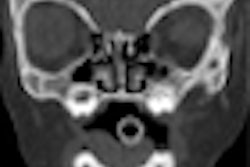

Hoang's group compared the radiation dose of conventional fluoroscopy-guided lumbar epidural steroid injections and CT fluoroscopy-guided lumbar epidural steroid injections using both clinical data and anthropomorphic phantoms. The researchers retrospectively reviewed dose parameters for 14 conventional fluoroscopy injections performed by one clinician and 42 CT fluoroscopy-guided injections performed by three clinicians (14 each) (AJR, October 2011, Vol. 197:4, pp. 778-782).

The study showed that absorbed radiation doses to the skin, small bowel, large bowel, and bone marrow were greater for conventional fluoroscopy than CT fluoroscopy. However, when the dose of the planning CT (scan range from L2 to S1) was combined with that of CT fluoroscopy, the dose was four times higher compared to conventional fluoroscopy.